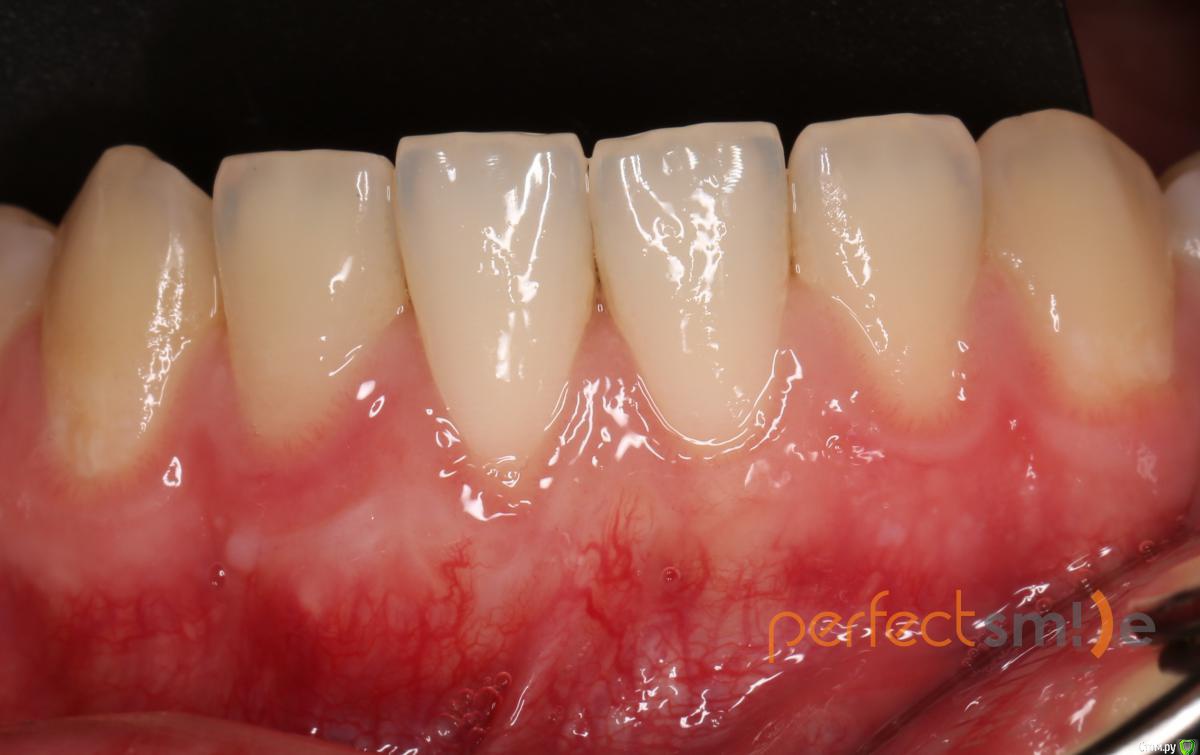

Bier Опубликовано 12 марта, 2020 Автор Поделиться Опубликовано 12 марта, 2020 Большой Зеленый, смотри ) 4 Ссылка на комментарий

Bier Опубликовано 13 марта, 2020 Автор Поделиться Опубликовано 13 марта, 2020 я вижу небольшой рецидив, но считаю, что все так и останется. Удовлетворительно.Более толстый трансплантат в такой ситуации рискован некрозом всего. В моем кейсе покрывной лоскут очень тонкий. Ссылка на комментарий

Irouil Опубликовано 13 марта, 2020 Поделиться Опубликовано 13 марта, 2020 Объективно - прикрепленки мало Но учитывая что было... На мой взгляд результат действительно удовлетворительный, смотреть надо что будет дальше, но даже если придётся повторять - условия будут лучше. Рубцов агрессивных нет, это главное. Ссылка на комментарий